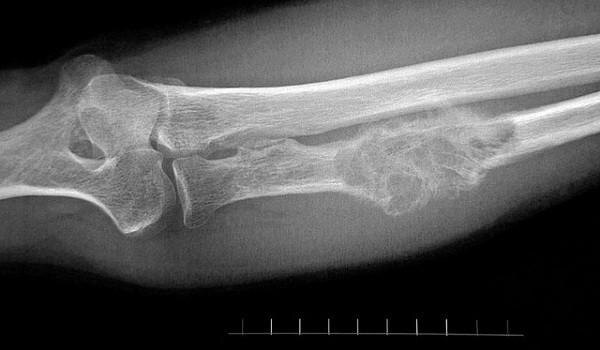

• Рентген — снимки пораженного участка позволяют определить нарушения структуры и повреждения кости.

• КТ — определение изменений костной ткани.

Кость размягчается, возможны частые переломы без больших нагрузок. Поставить диагноз только по симптомам невозможно, необходимы точные методы диагностики.